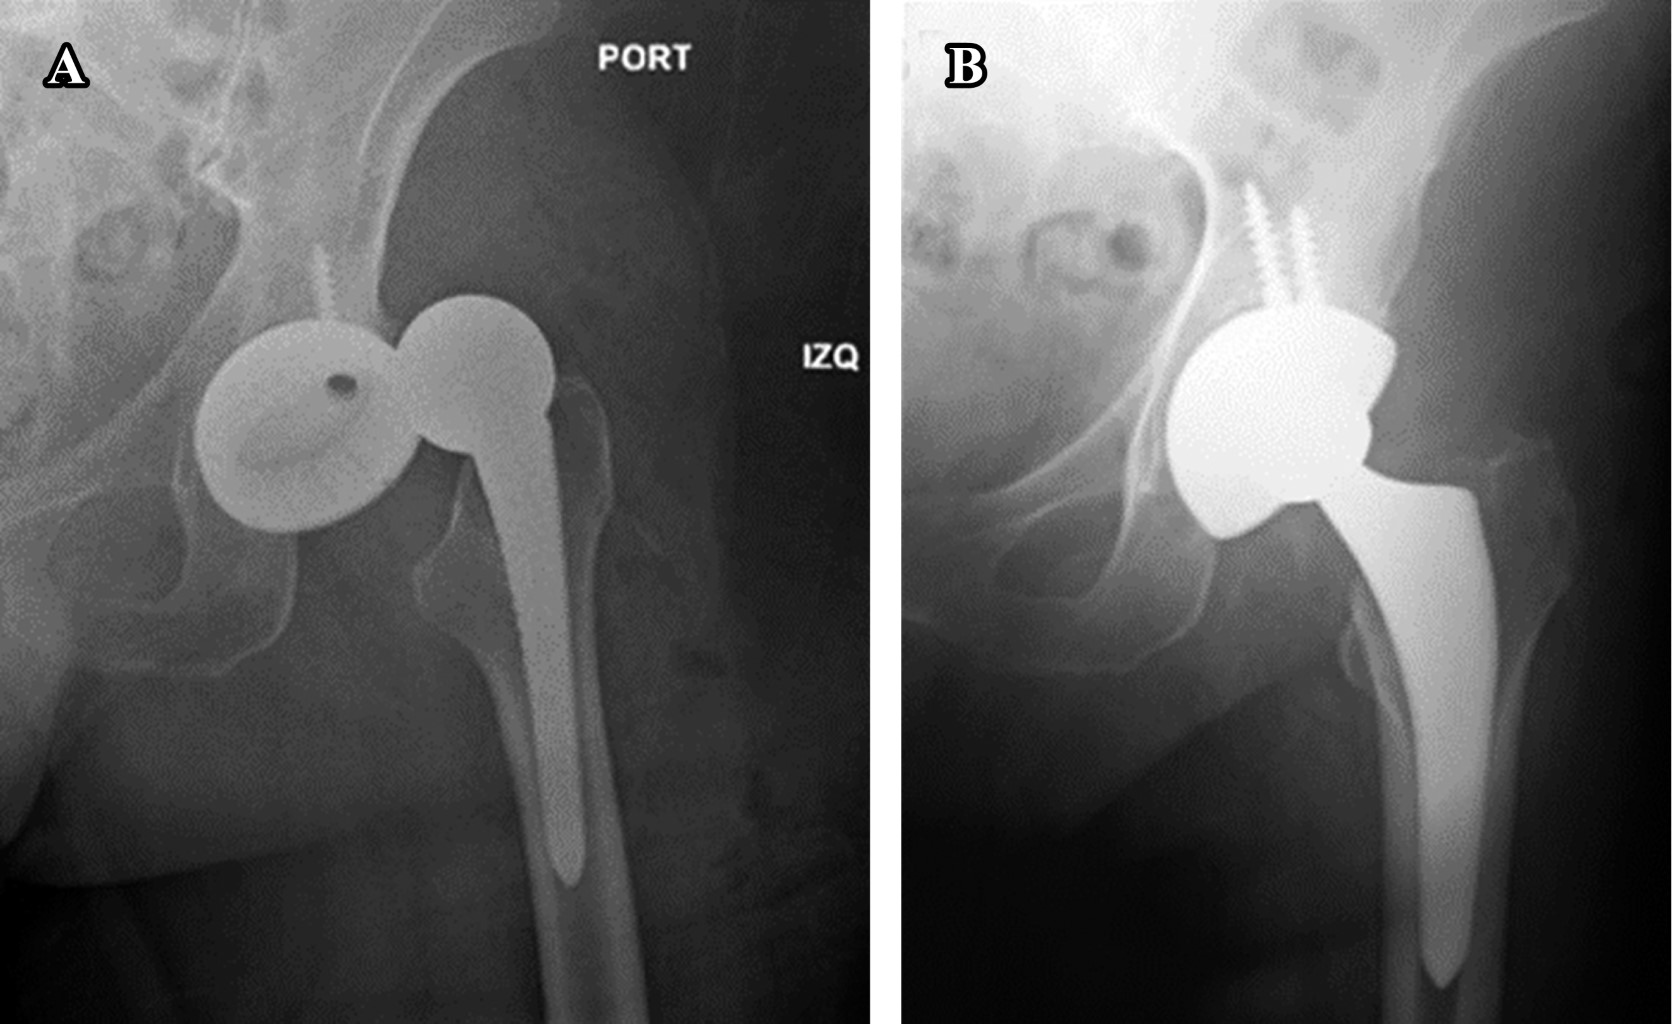

Cup orientation and preparation are challenging when first starting to use this approach if the surgeon is used to performing THA with the patient in a lateral decubitus position. In some cases, only a limited view of the anterior acetabular wall can be obtained, making cup placement more difficult, especially concerning the assessment of reaming. The reamers are introduced over the anterior femoral shaft with the patient in the supine position. Great caution must be used to avoid levering the reamer on the femur, as doing so could lead it to move anteriorly and risk reaming away the anterior wall. Also, cup version and abduction angles are best determined relative to the native pelvis and can be easily determined by palpating both anterior superior iliac spines. Having the patient in the supine versus the lateral decubitus position is a definite advantage in such determinations. A common error is to insert the cup with too much anteversion inadvertently. There is a tendency to hold the cup inserter too vertically, which imparts excessive anteversion to the component relative to the native pelvis. The use of fluoroscopy when first learning the procedure will avoid these issues and its position during the reaming and cup insertion. The image intensifier should be placed and positioned, supervised by the surgeon to ensure the correct images match the ap pelvis projection according to the obturator foramen on the screen. Sometimes it is necessary to angle the C arm 10 degrees caudally to obtain the matching image. The position of the C arm must be reevaluated several times during the surgery to avoid a false anteversion view and subsequent malpositioning of the cup16,17 (Figure 3A-B).

EARLY POSTOPERATIVE COMPLICATIONS

Specifically, the three main early complications are dislocation, infection, and periprosthetic fractures. Early dislocations, as with any other approach to the hip, are usually a product of component mispositioning. Unless the acetabular or femoral components have been considerably retroverted upon implantation, dislocations following the DAA are typically anterior. Due to the musculature not being detached posteriorly or anteriorly, as long as the components are well positioned, it is postulated that this approach enhances inherent stability compared with other approaches. Reported dislocation rates reported in the literature were 0.96 to 1.5%. These rates are significantly lower than the rates generally quoted for other approaches22,23 (Figure 6A-B).